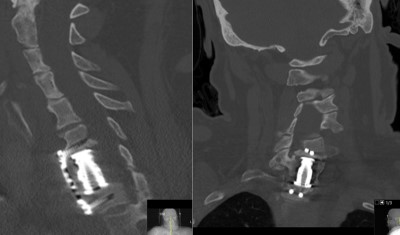

Intraoperative fluoroscopic images (lateral projections) taken during the C7 corpectomy and fusion procedure. Left image shows localizing needle in the C7-T1 disc space. Right images show the expandable interbody biomechanical device (aka cage) being applied. The upper image shows the top of the cage while the lower image shows the bottom.

- Post-op